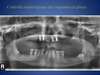

Prothèse complète amovible stabilisée sur barre d’Ackerman